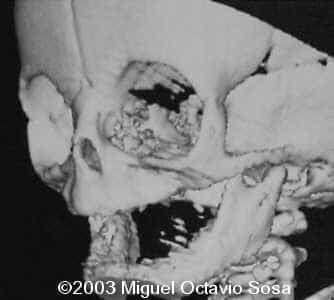

A female newborn was delivered at 38 week, by cesarean section due to breech presentation. Size of right eye is bigger than left, and there is total absence of the right nostril. Apgar 9 at birth. No complications during postpartum. Newborn is actually under study by plastic surgeon.

These are the 3D CT reconstruction.